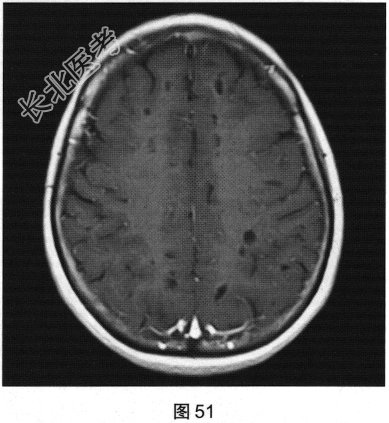

- 多项选择题2.[提示]患者行FLAIR、DWI及增强扫描,见图45~图54。该患者MRI影像的主要阳性表现有( )

A、增强后扫描病灶无强化

C、双侧放射冠及半卵圆中心多发条状、圆形及卵圆形异常信号灶

E、病灶呈长T1、长T2信号,FLAIR为低信号,DWI为低信号,ADC为高信号